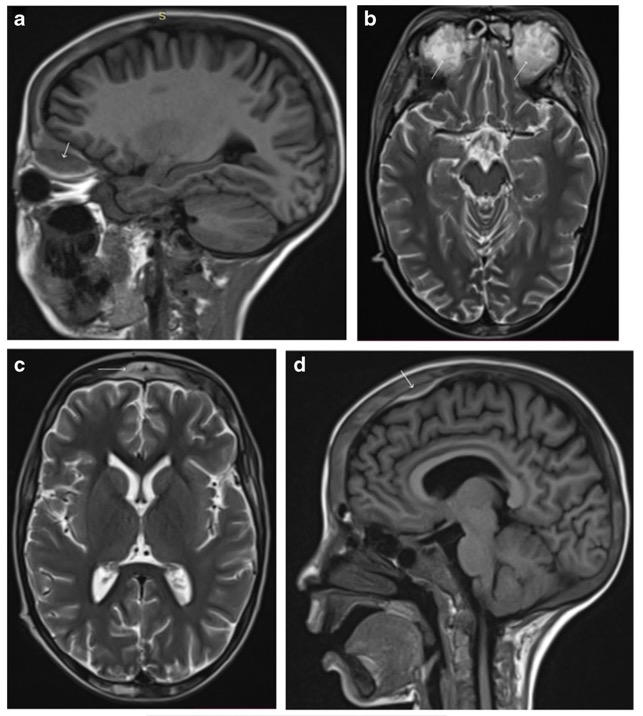

Hématomes sous-périostéaux bilatéraux

Les infarctus osseux peuvent parfois impliquer l'orbite lors d'une crise vaso-occlusive

=> hématomes sous-périostéaux

Diagnostic: CT C+ exclut infection

TRT: décompression chirurgicale